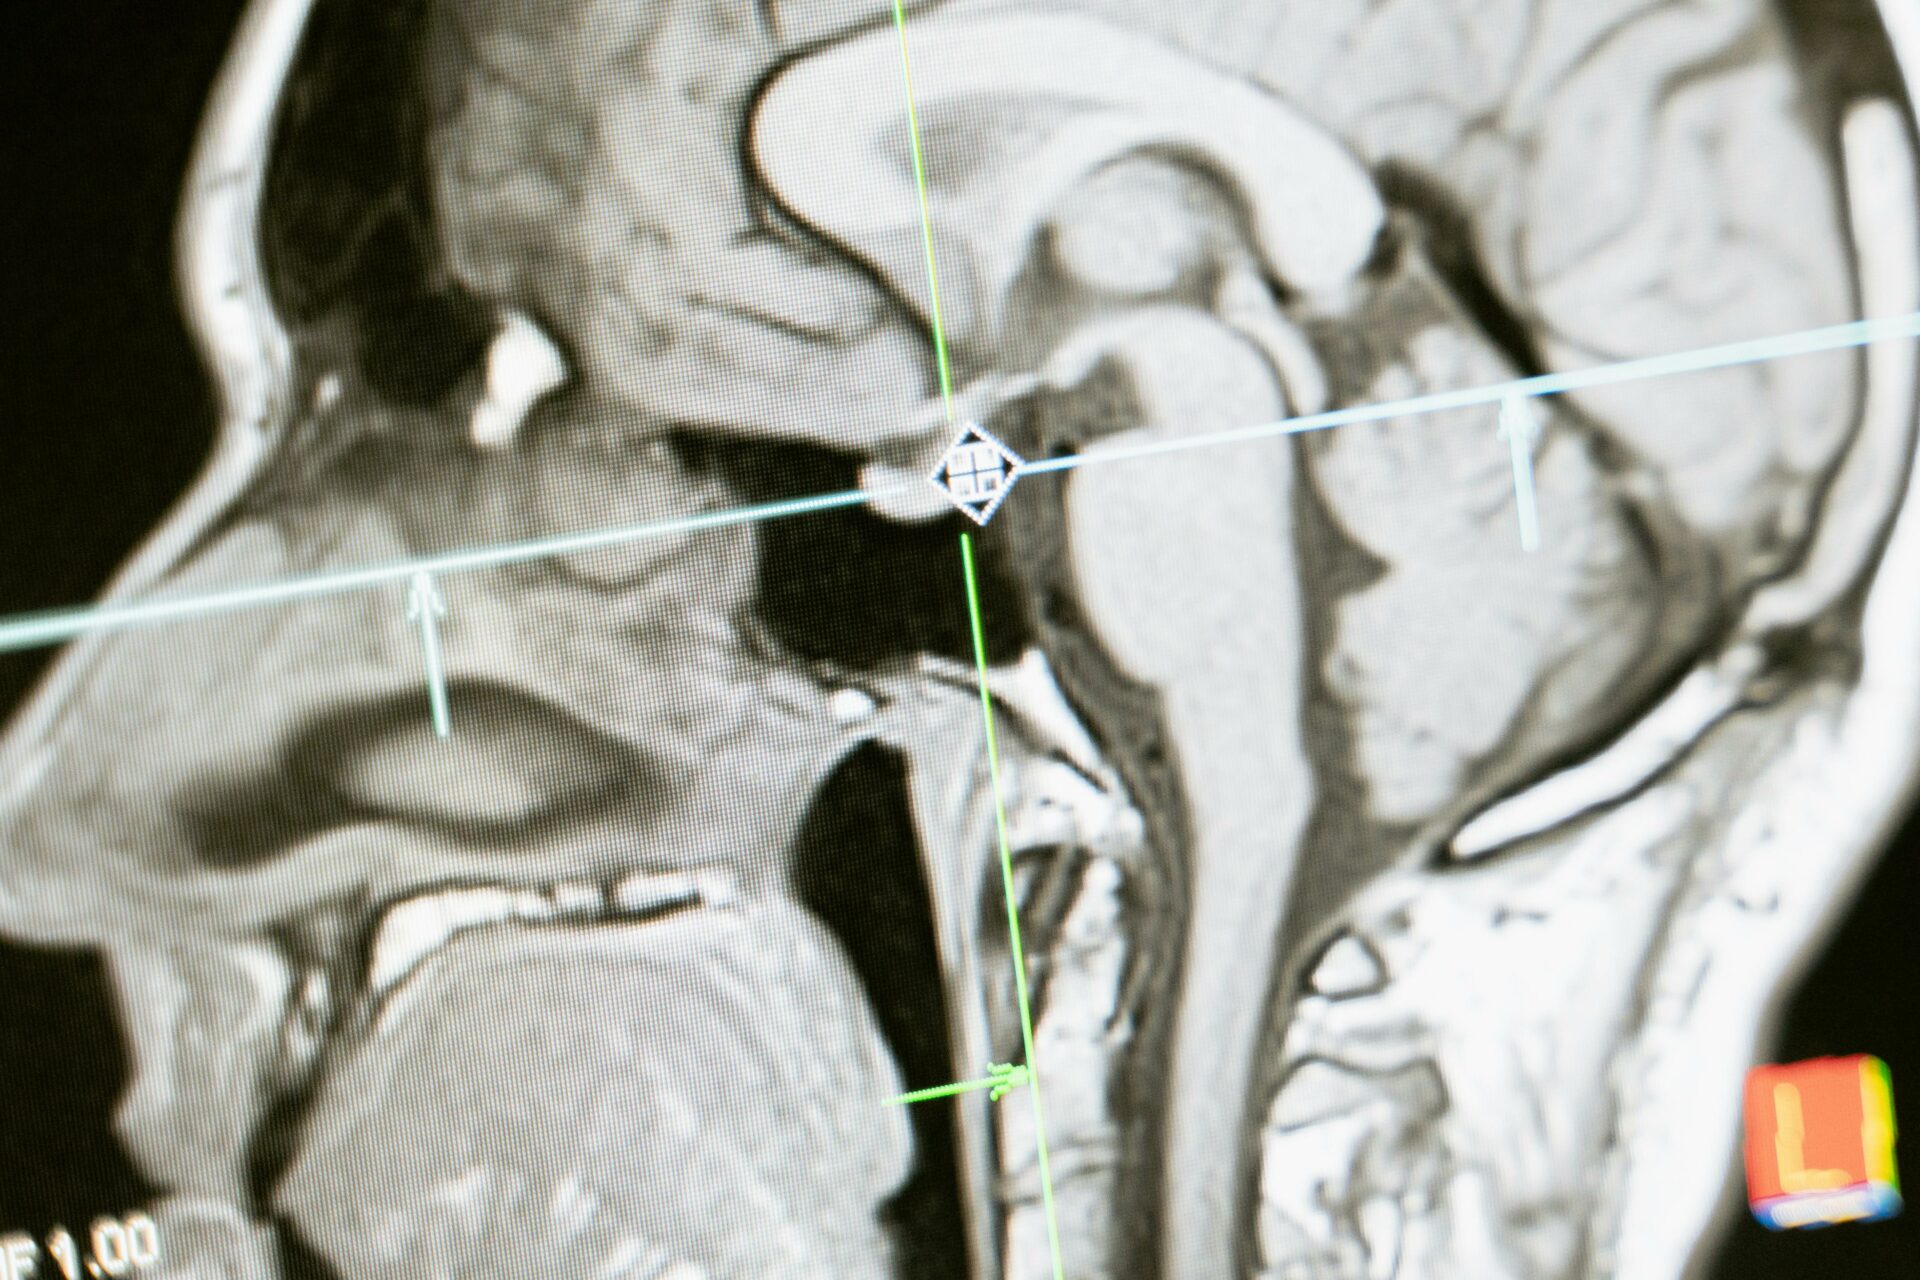

Според современите невропсихолошки објаснувања, déjà vu се појавува кога одредени елементи од ситуацијата активираат чувство на познатост во дел од мозокот во областа на слепоочниците, наречен периринален кортекс. Тоа може да биде предизвикано од сличности со претходни искуства.

Потоа хипокампусот (структура клучна за меморијата) не успева да најде конкретно сеќавање што би го објаснило тоа чувство.

На крај, овој „конфликт“ го препознаваат делови од фронталниот кортекс, како предниот цингуларен кортекс и медијалниот префронтален кортекс. Токму ова создава чувство дека нешто веќе сте доживеале, иако знаете дека не сте.

Истражувањата покажуваат дека кога déjà vu се симулира во лабораториски услови преку игри за меморија, токму овие фронтални делови на мозокот покажуваат зголемена активност.